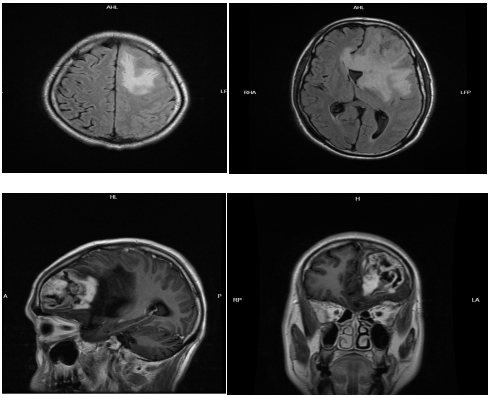

2023年4月15日,剛參加完清華大學(xué)第三屆“公立醫(yī)院高質(zhì)量發(fā)展”論壇活動的廣東省惠州市第三人民醫(yī)院院長、神經(jīng)醫(yī)學(xué)中心主任、神經(jīng)外科學(xué)科帶頭人李雪松博士連飯都顧不上吃,立刻趕往機場,他跨越近兩千公里奔赴貴州省冊亨縣,一臺患者和家屬及所有醫(yī)護(hù)人員都萬分期待的腦瘤切除手術(shù)等待著他。

“腫瘤位于左側(cè)大腦半球,屬于功能區(qū),容易引起語言和肢體運動的障礙。手術(shù)盡可能地要把它完整切除,同時要保護(hù)正常的功能不受影響?!崩钛┧刹┦恐赋觥?/span>

手術(shù)過程也是教學(xué)過程,惠州三院專家團隊充分發(fā)揮“傳幫帶”精神,從手術(shù)體位的擺放、切口入路、手術(shù)技巧等方面,為冊亨縣人民醫(yī)院同行提供技術(shù)解說??吹嚼钛┧刹┦烤康氖中g(shù)技巧,聆聽專家的精彩講解,手術(shù)現(xiàn)場的醫(yī)護(hù)人員受益匪淺。

開展幫扶以來,通過設(shè)立博士名醫(yī)工作站,開展醫(yī)療學(xué)術(shù)和專科培訓(xùn)3153人次,培養(yǎng)技術(shù)骨干人才14人,新增醫(yī)療新技術(shù)新項目36項,開創(chuàng)了冊亨“前列腺癌腫瘤電切手術(shù)”“顱內(nèi)腫瘤手術(shù)”“隔空診療”等多項先例。醫(yī)療幫扶團隊深入村(社區(qū))開展義診和調(diào)研,結(jié)合白內(nèi)障、心血管等集中病癥,精準(zhǔn)開展“健康心”“健康明”等健康冊亨“五項活動”,惠及5600余名群眾,書寫了“讓95名白內(nèi)障患者重見光明”的感人故事。